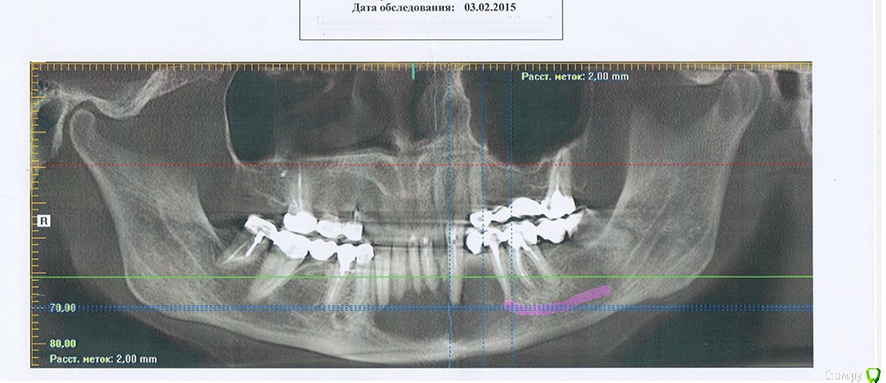

Helenka Опубликовано 29 февраля, 2016 Поделиться Опубликовано 29 февраля, 2016 Здравствуйте! В октябре 2014 года была сделана операция по удалению кисты нижней челюсти. Операцию делали в Москве. Я сама из Волгограда. У меня есть снимки после операции сделанные в феврале 2015 года.И снимки в феврале 2016 года.Видно, что идет формирование кости. В связи с тем, что до Москвы доехать никак не получается, а местные стоматологи как-то жмут плечами, может что посоветуете? У меня вопрос: перед передними зубами нижней челюсти нет на данный момент кости. Она нарастет со временем или надо провести какую-нибудь дополнительную операцию. И те темпы с которыми у меня увеличивается толщина кости - это нормальная скорость или слишком медленно? Ссылка на комментарий

red_butler Опубликовано 1 марта, 2016 Поделиться Опубликовано 1 марта, 2016 Прослеживается положительная динамика, необходимости в повторном вмешательстве не вижу. Ссылка на комментарий